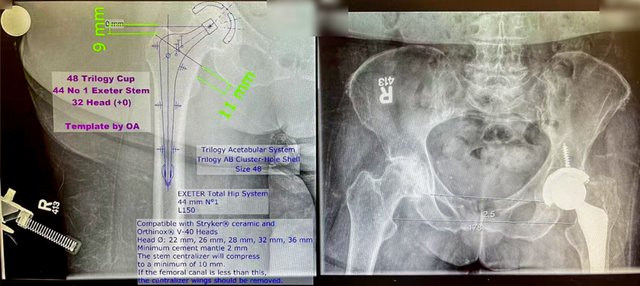

2. 高风险手术患者占比较多,因为人种的差异,这里的患者,高BMI的比例相当高,部分患者甚至接近50!!(18.5 kg/m² ≤ BMI < 24 kg/m² 正常范围值,≥28 kg/m²属于肥胖)对骨关节科医生而言是前所未有的挑战,但是SunneyBrook的骨科专家经过详细的术前讨论、术前规划后,小心而细致地进行了关节置换或者翻修手术,术后创面直接负压吸引(类似于国内的VSD)2周,疗效较好。

3. 植入材料的选择上,既往存在的观念是,国外的一定选用最先进最好的材料,其实并不是,很欣赏Dr.Nousiainen的话:The skilled is the best。他们选择的大部分都是多年使用成熟的植入物,对其特性和适应症非常熟悉,出现任何情况知道如何处理,并不会贸然使用所谓最新最贵的材料(甚至有一款目前国际流行假体就是我所在医院的教授发明并使用的)。